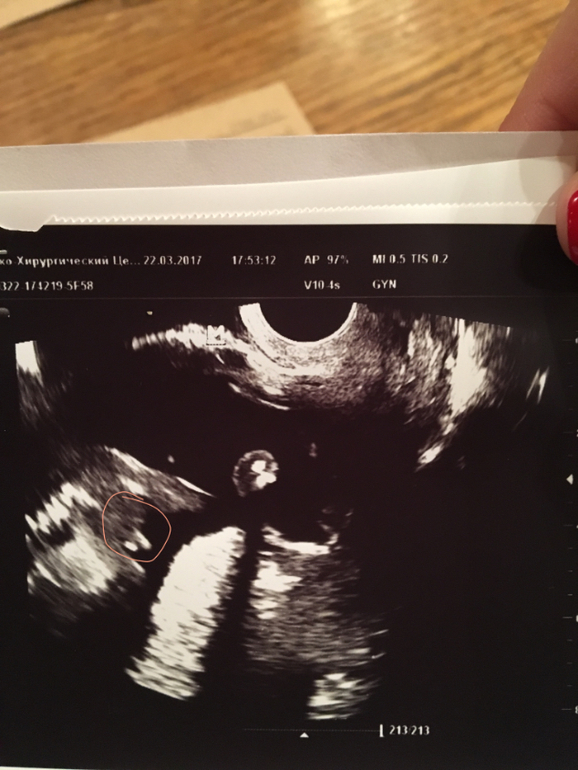

Мои неделькиПол малыша. Девочки, помогайте)))) мне ничего не понятно) фото под кат. Обвела то, что на мой взгляд показывает мальчик или девочка. П.С. На первом фото мне вообще ничего непонятно

Да я 5000 за второй скрининг заплачу в ЦИРе через 2 нед)) Там я думаю все хорошо разглядят. Вчера в попыхах пошла в одну из ближайших клиник, т.к хотела сделать подарок мужу к д.р. А в итоге толком то и непонятно

Потому что не совсе уверена в том, что врач прав.у нег было первое посещение, вот и закрались сомнения. Т.к она очень долго рассматривала